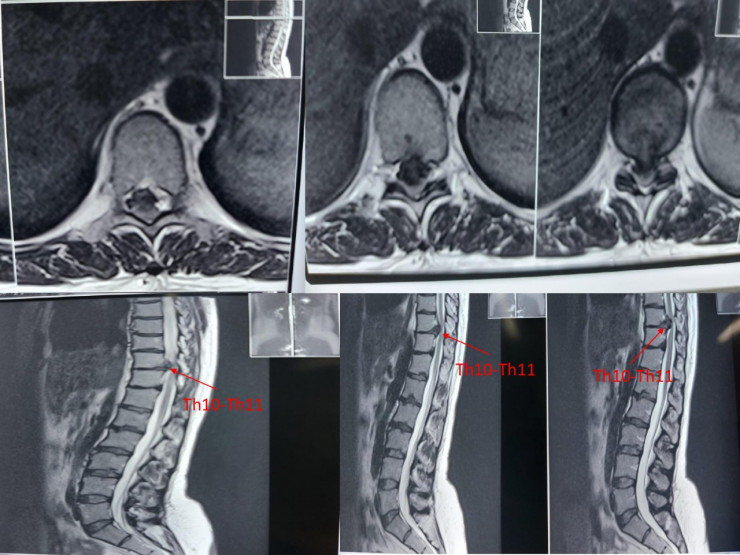

Алматинские нейрохирурги успешно провели сложную операцию пациентке с редкой патологией, передает корреспондент Tengrinews.kz. В отделении спинальной нейрохирургии городской клинической больницы № 7 проведена операция по микрохирургическому удалению грыжи диска грудного отдела позвоночника.

Как отмечают специалисты, грыжи могут встречаться в шейном, грудном и поясничном отделах позвоночника. Наиболее редкая и опасная из них - межпозвонковая грыжа грудного отдела позвоночника, она встречается лишь в 1 проценте из всех случаев.

Фото предоставлено пресс-службой ГКБ № 7

"Грыжа грудного отдела возникает, когда фиброзное кольцо разрывается в результате травмы или постепенного истончения и разрушения стенок. В образовавшиеся полости проникает студенистое ядро. Развивающаяся деформация (выпячивание позвоночного диска) приводит к защемлению нервных окончаний спинного мозга и нарушению кровообращения в спинномозговом канале", - пояснили специалисты.

По словам заведующего спинальным нейрохирургическим отделением № 1 ГКБ № 7 Бахыта Аглакова, пациентку продолжительное время беспокоили постоянные ноющие боли в спине, слабость в нижних конечностях, онемение с уровня пупка и обеих ног. Она с трудом передвигалась по дому.

"Операция выполнена на высоком уровне. В послеоперационном периоде нижний парапарез регрессировал полностью, пациентка передвигается самостоятельно, боли в грудопоясничном отделе позвоночника купировались. Чувствительные нарушения также регрессировали", - рассказал Аглаков.